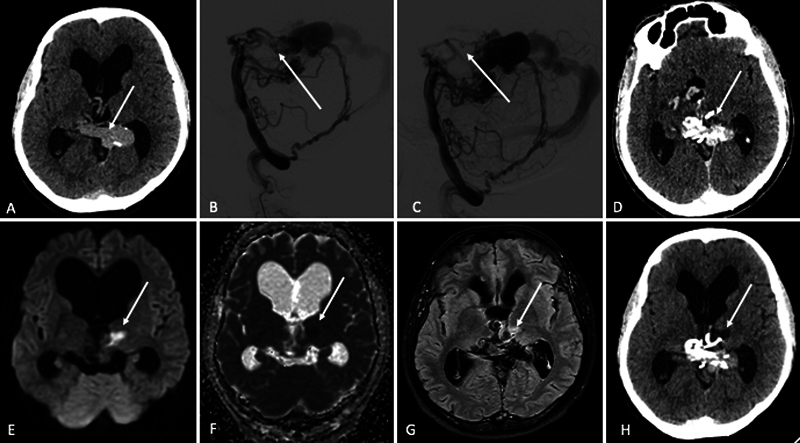

The thalamus, a gray matter structure, is a crucial relay for various afferent and efferent pathways in the brain. It receives its primary blood supply from the thalamoperforating and thalamogeniculate branches of the posterior cerebral arteries. Damage to the thalamus can lead to classical sensorimotor and amnestic syndromes, as well as neuro-ophthalmological manifestations, including vertical gaze palsy (VGP), pseudo-abducens palsy, skew deviation, cerebral ptosis, and Horner's syndrome. While most cases of VGP are self-limiting, some can persist, significantly affecting daily life. This report describes a case involving a 33-year-old man with a vein of Galen malformation who underwent embolization and subsequently developed VGP in the postoperative period. This complication was attributed to a medial thalamic infarct. Notably, the patient experienced spontaneous resolution of the gaze palsy within 3 months.